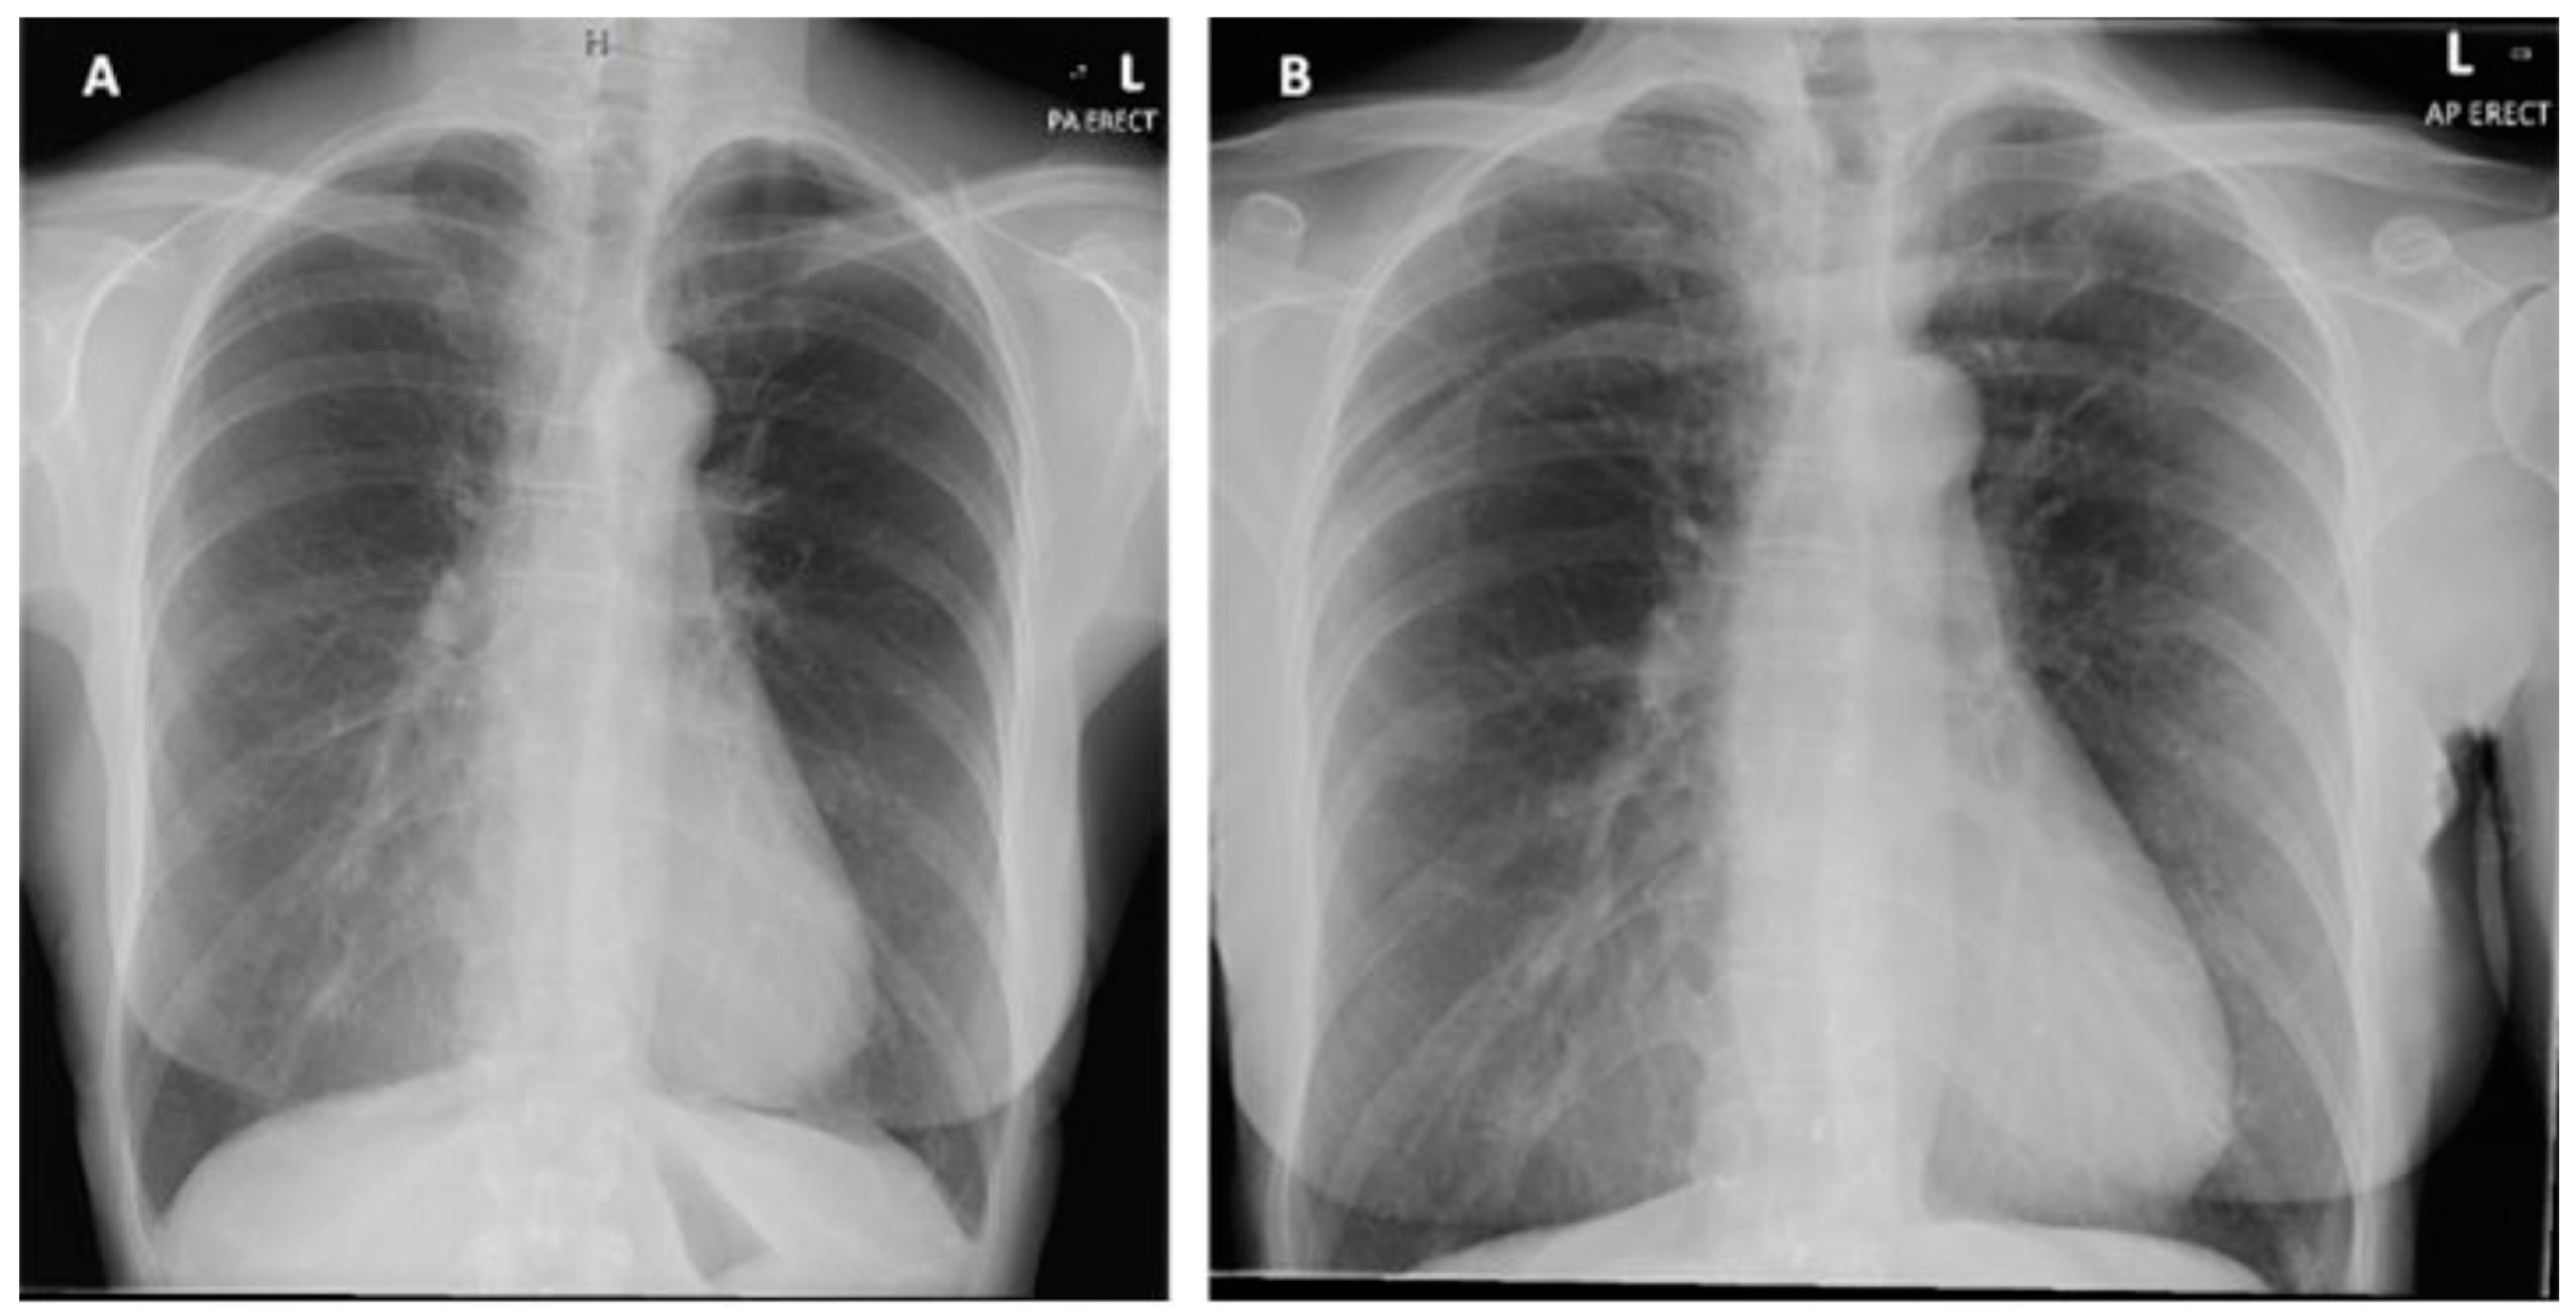

Figure 5.

When using bubble transthoracic echocardiogram, bubbles will be visualized entering the right heart using the apical four-chamber or subcostal views. Once there is complete opacification of the right atrium (RA), cardiac cycles are counted [5]. In patient without any type of shunt present, no bubbles should appear in the left heart. If, bubbles appear in the left atrium (LA) after three cardiac cycles, an intracardiac shunt is likely present.